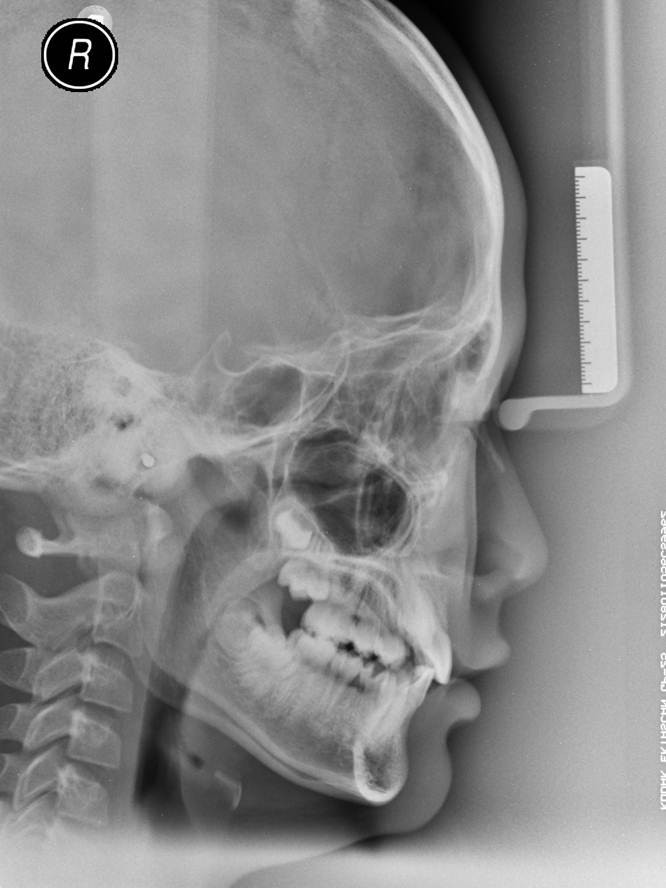

检查:颌面部左右对称,侧貌平直美观,下颌发育良好。 口内6-6恒牙列,右侧磨牙关系开始远中,左侧磨牙关系基本中性, 13、23均位于粘膜下,可扪及牙冠形态。高位阻生,13几无萌出间隙, 上颌重度拥挤9mm,下颌轻度拥挤2mm。 下牙列中线左偏2mm 乳牙多颗滞留史

诊断:Angle II 类1分类亚类 骨性I类 水平生长型 治疗思路:对于该例重度拥挤的患者,属于拔牙适应症, 然而,由于患者10岁,处于替牙后期,第二磨牙均未萌出, 我们通过合理设计可以不拔牙逆袭,保存完整牙列。 传统意义上,推磨牙向后的手段可以为不对称口外弓或摆式矫治器。 前者严重依赖患者配合,或者治疗体验差,复诊时间长。 还好,生逢其时的患者赶上了自锁矫治的曙光, 在18个月的治疗后,我们得到了下图中的结果。